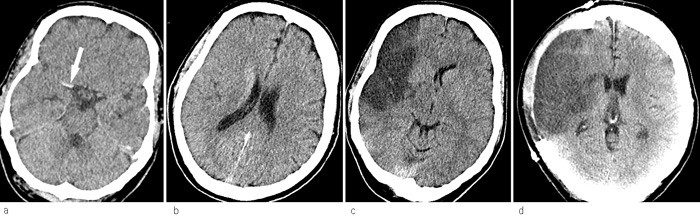

Trombemasser i a. cerebri media kan ses på CT uten kontrast hos én av fire pasienter med kliniske tegn til infarkt i a. cerebri medias forsyningsområde (fig 1a) (25). En hyperdens a. cerebri media varsler sekundær forverring med en sensitivitet på 89 % og en spesifisitet på 60 % (26). Tidligere tegn til hjerneødem ved CT ses som hypodensitet i basalgangliene og ved at grensen mellom grå og hvit substans blir vanskeligere å definere på syk side (25). Andre tidlige tegn er redusert volum av fissura Sylvii og utplanert kortikalt relieff. Etter 3 – 6 timer er det hypodensitet i infarktområdet, på figur 1a og figur 1b ser man at et økende hjerneødem komprimerer sideventrikkelen (25). Figur 1c viser hvordan midtlinjen blir forskjøvet. Ventrikkelen på motsatt side utvides når forskyvningen obstruerer tredje ventrikkel og foramina Monroi.